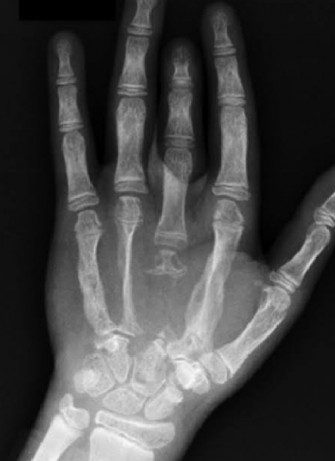

La maladie de Gorham-Stout (GSD), également connue sous le nom de maladie de l’os fantôme, est un trouble lymphatique rare, dans lequel la destruction osseuse progressive se produit en raison de la pr...